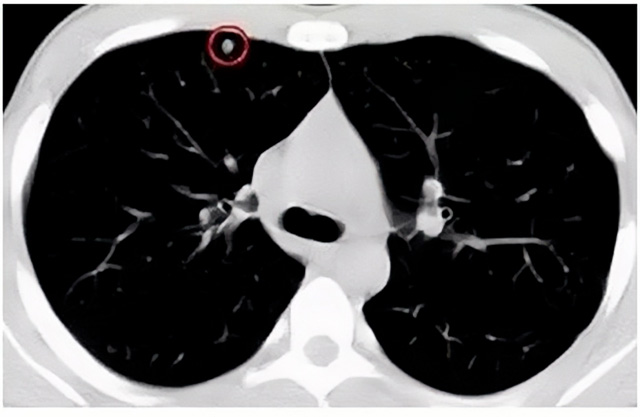

移動CT體檢車可以做肺部檢查。隨著多層螺旋CT肺部低劑量掃描的臨床應(yīng)用,目前很多人選擇肺部CT作為常規(guī)檢查項(xiàng)目,較大地提高了肺結(jié)節(jié)的檢出率。如果檢查發(fā)現(xiàn)肺部有肺結(jié)節(jié)是磨玻璃型的,小于5mm的微小結(jié)節(jié),大部分都是良性的。如果達(dá)到1CM以上的,很有可能有肺癌的機(jī)率。根據(jù)其內(nèi)密度不同可分為磨玻璃結(jié)節(jié)、實(shí)性結(jié)節(jié)、部分實(shí)性結(jié)節(jié)。根據(jù)其大小可分為肺大結(jié)節(jié)、小結(jié)節(jié)和微小結(jié)節(jié)。如果是炎癥性肺結(jié)節(jié),幾個(gè)月后復(fù)查有變化變小就不用做手術(shù)。如果CT再次復(fù)查結(jié)節(jié)沒有變化,沒有縮小就需要升級做病例檢查。病理檢查的確診性是最高的。是有沒患癌的標(biāo)準(zhǔn)。檢查發(fā)現(xiàn)早的話,規(guī)范手術(shù)治療,手術(shù)后5年的存活率很高的。肺癌這個(gè)要早發(fā)現(xiàn)早治療。

現(xiàn)在的移動CT體檢車的分辨率比X光高,CT掃描的圖像越來越薄顯像更清晰,檢查更準(zhǔn)確。得到了普及,肺結(jié)節(jié)的測出率很高的。但是顯浩告訴大家,肺結(jié)節(jié)不等于肺癌。雖然很多是良性,但是很多肺癌都是肺結(jié)節(jié)發(fā)展來的。 必須定期檢查復(fù)查。磨玻璃結(jié)節(jié),肺癌的機(jī)率較高。肺癌是惡性腫瘤病死率最高的。除了環(huán)境,遺傳,等因素。吸煙,從事煙霧工作行業(yè)的人員比較危險(xiǎn)。發(fā)病比例高。肺部疾病早發(fā)現(xiàn)早治療,依舊是肺部疾病的治療標(biāo)準(zhǔn)。

一旦CT檢查發(fā)現(xiàn)肺結(jié)節(jié),若不規(guī)律復(fù)查,檢查等同于白檢。所以在復(fù)查中,如果結(jié)節(jié)中發(fā)現(xiàn)有增大的趨勢,或大小發(fā)生了變化,我們必須提請注意及時(shí)治療,不要掉以輕心。移動CT體檢車的普及化,讓肺部檢查更準(zhǔn)確更高效。發(fā)現(xiàn)肺結(jié)節(jié)時(shí),及時(shí)就醫(yī)并進(jìn)行專業(yè)評估是確保準(zhǔn)確分類和采取適當(dāng)措施的關(guān)鍵。